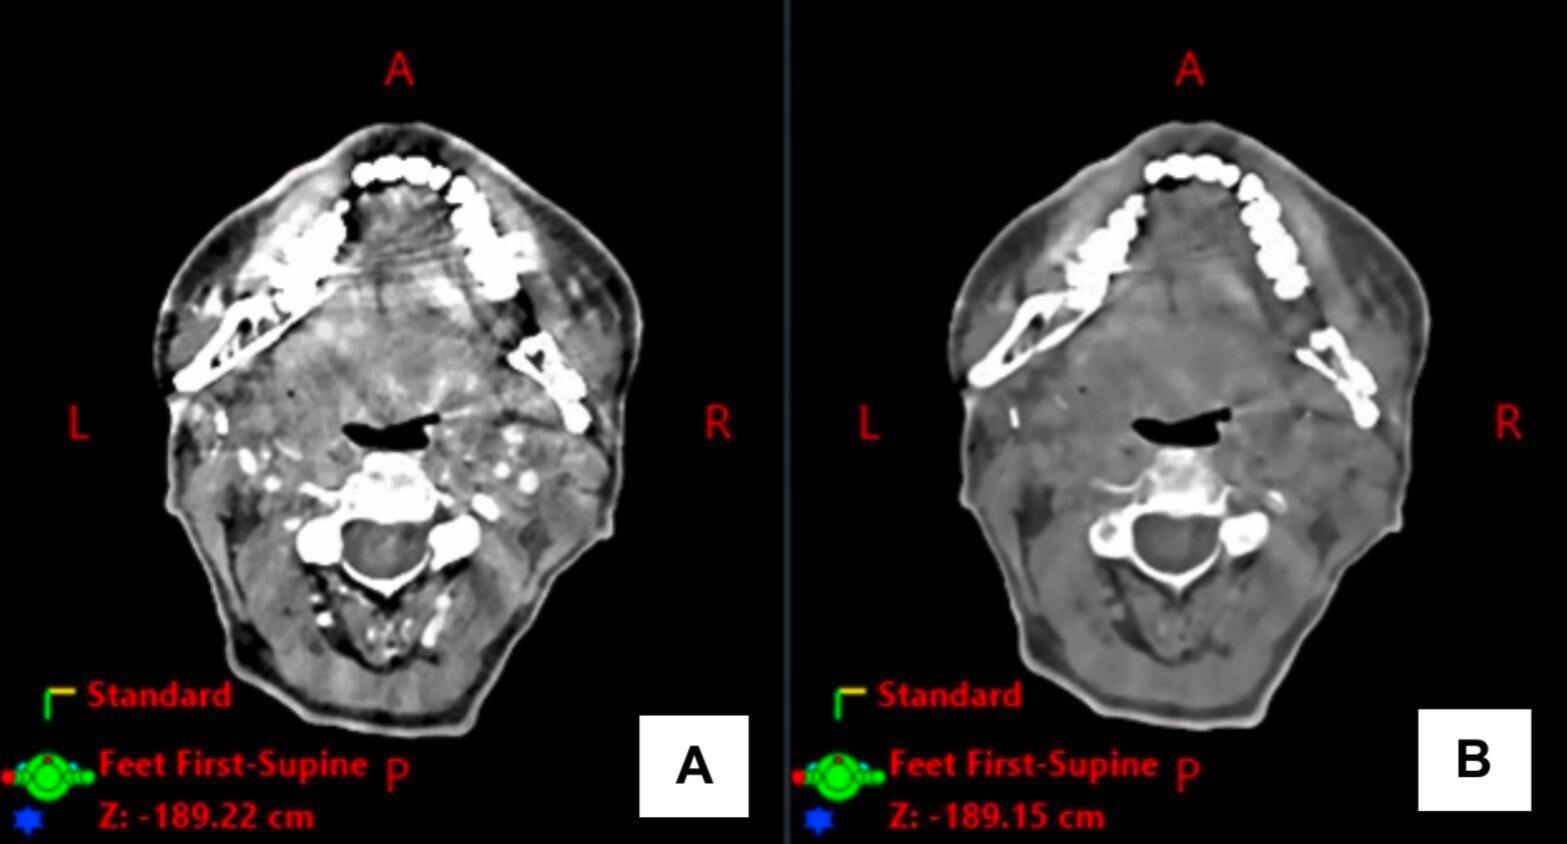

Pour cette étude, les chercheurs ont inclus douze patients (neuf hommes, trois femmes, âge moyen 63,9 ans) atteints d'un cancer dont les volumes cibles étaient situés à proximité d'implants radio-opaques (implants dentaires, amalgames ou reconstructions de la mâchoire en titane après une chirurgie tumorale). « Onze tumeurs étaient des carcinomes épidermoïdes, et l'une était indifférenciée, précisent les auteurs. La tumeur primaire était principalement localisée dans la cavité buccale. Un patient était classé au stade III, et onze étaient classés au stade IV. » Les patients ont passé un scanner conven